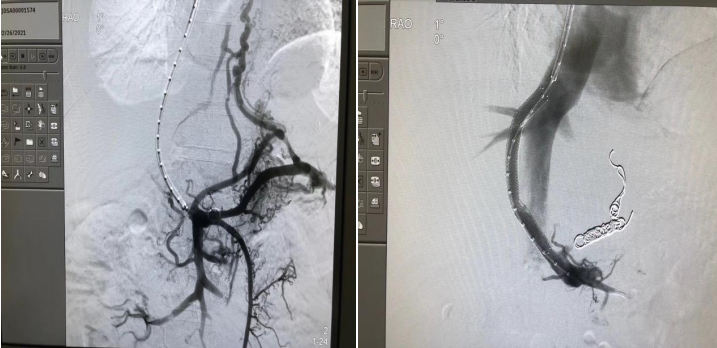

保障肝硬化失代偿期患者的生存,在很大程度上依赖于对门静脉高压的控制。门静脉高压的治疗除内镜及药物治疗外,介入技术在门脉高压诊治过程中正发挥着越来越重要的作用,肝胆胰介入手术之一-经颈静脉肝内门体静脉分流术(TIPS)已成为治疗门脉高压性消化道出血及肝硬化顽固性腹水的重要方法之一。TIPS治疗既可以治疗出血,又可以治疗门脉血栓,使门静脉血栓逐渐消失,不影响后续肝移植,也可以减少肝移植后门静脉血栓形成风险。

近30年来,TIPS技术发展可谓一波三折,随着近年来各种新材料、新技术的推广应用,介入又迎来了春天,TIPS和其他介入诊疗技术已经不断渗透到各个领域,取得令人满意的疗效,成为最具活力的学科。 “5g影院 肝胆胰介入中心”成立以来,每年完成TIPS手术近200例, 稳居全国前列。建立了浙江省最大TIPS病例库,已成为浙江省乃至全国最大的TIPS技术推广中心之一。本中心同时为中国大陆首批TIPS新型专用支架应用单位,止血有效率达95.7%。腹水缓解有效率达90%。孙军辉主任团队已经在省内外31家医院推广开展或合作提升TIPS技术,惠及大量肝硬化门脉高压患者,多次受邀在国内省内外学术大会做TIPS专题报告,并协助省内医学中心建立区域TIPS技术推广中心。